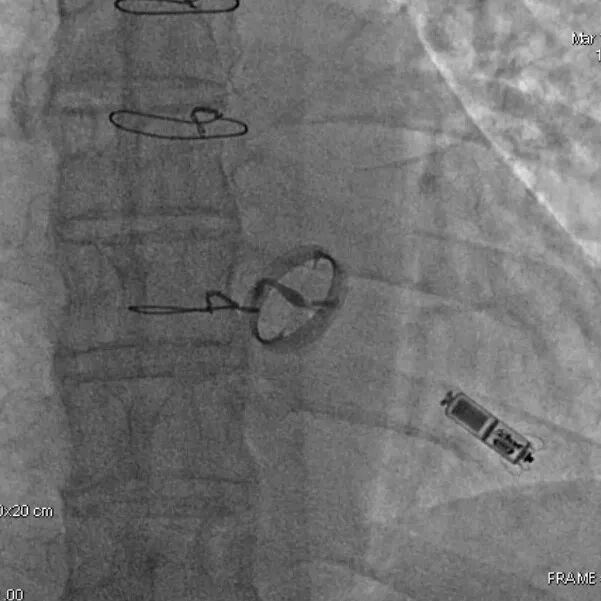

2015年,中国医学科学院阜外医院参与了Micra全球上市前临床试验,总共入组了5名患者。该临床试验为全球多中心、非随机、单臂上市前临床研究,旨在评估Micra VR无导线起搏器的安全性和有效性。该项研究的结果发表在2015年新英格兰医学杂志上,研究结果表明,Micra VR无导线起搏器手术成功率为99.2%,其不良事件发生率相对于传统起搏器降低了48%。

5名患者中, 2名患者因恶性肿瘤及肺部感染分别于2019年和2022年离世。3名患者随访已达到10年,相关数据整理如下

Micra无导线起搏器自2015年3月在国内首次使用于临床,中国最早获益于无导线疗法的患者在长达十年的随访周期内,展现出了优秀的长期电学参数表现。其中阈值、阻抗、感知都在正常范围以内,起搏器寿命也达到预期。无导线起搏器为患者提供了长久、安全、可靠的治疗选择。随着临床应用的增多和使用时间的延长,相信有更多临床数据可以说明无导线起搏器在中国患者中的安全性和有效性。